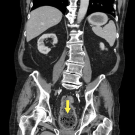

A previously healthy 9-year-old boy developed acute upper left quadrant and epigastric abdominal pain, nonbloody nonbilious vomiting, and decreased oral intake.

12/04/2024